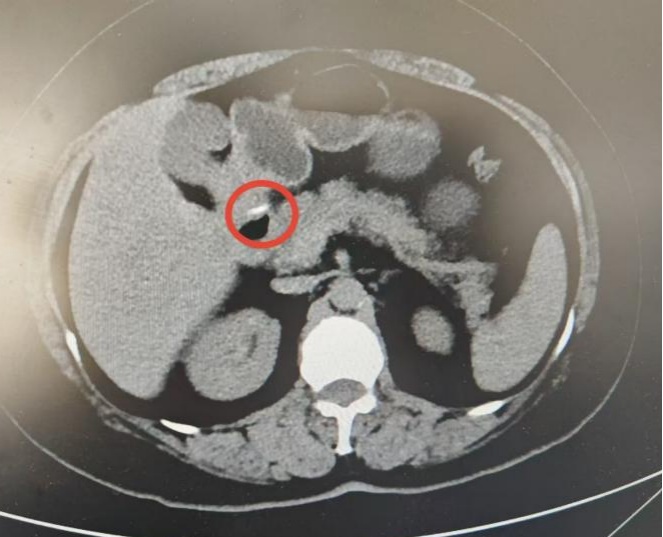

经腹部CT检查发现,有一个刺状条形异物穿透了王女士的胃后壁,部分位于壁外,显然是出现胃穿孔。如果不及时取出,可能会穿透胃后方的胰腺,引发内出血、胰液性腹膜炎等严重并发症。

腹部CT显示刺状条形异物穿透胃后壁。